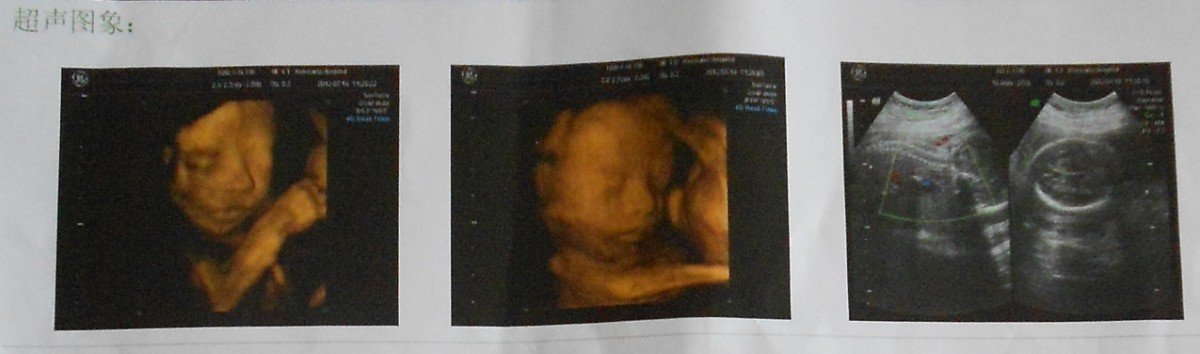

根据以下B超及四维彩超数据显示,宝宝是男孩还是女孩?

孕8周时B超数据:    超声所见:子宫前位,体积增大,轮廓清,宫肌回声均匀,宫腔内可见一大小约45×17mm妊娠囊,囊内可见卵黄囊。可见胚芽(长15mm)及原始心管搏动。双侧附件未见异常回声。超声提示:宫内早孕,胚胎存活(大小约8W) 孕24周四维彩超数据:宫内妊娠,单活胞,符合24W0d超声所见:    经四维动态超声检查:宫内可见一胎儿回声,可见胎心搏动及胎动。    胎儿超声测值:双顶径57mm,头围203mm,腹围209mm,小脑横径23mm,后颅窝池5mm,股骨长41mm,肱骨长38mm,羊水暗区最大前后径:51mm,羊水指数12cm。胎儿体重:670±98g。    胎盘:附着于子宫后壁,厚度:25mm,胎盘下缘距宫颈内口测值在正常范围,脐带连于胎盘胎儿面。    脐动脉:双脐动脉可见,脐动脉收缩期血流峰值流速:28.3cm/s,脐动脉舒张末期血流最低流速:8.2cm/s,RI:0.7,S/D:3.4,胎心率:154bmp。